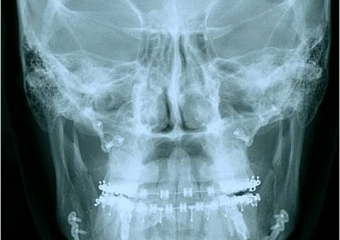

Telerradiografia frontal inicial

Telerradiografia frontal após a cirurgia